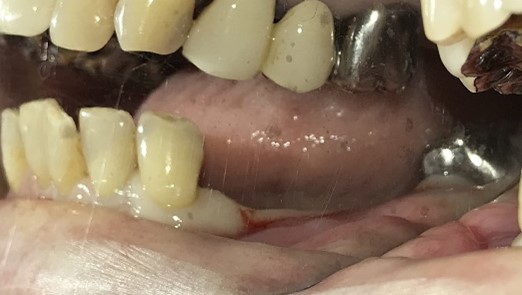

上下、歯がないところに入れ歯を作ったが、使っていない。インプラント治療をしてほしい。

上顎4本残っている歯を抜歯し、インプラントを6本埋入。下顎、右下2本、左下1本埋入。

上顎3本は、もし義歯で対応する場合であれば、保存してマグネット義歯の支台として活用します。しかし、患者さんが義歯ではなくインプラント治療を希望され、かつ、見た目が自然でよく嚙めるようになることが最優先事項でしたので、相談したうえで3本の歯は積極的に抜歯しました。

治療後、「インプラント治療に満足しています。食事が楽しくなりました。スタッフの方の説明がわかりやすかったです。1年間ありがとうございました。」と、とてもうれしくなる感想を書いていただきました。

Before